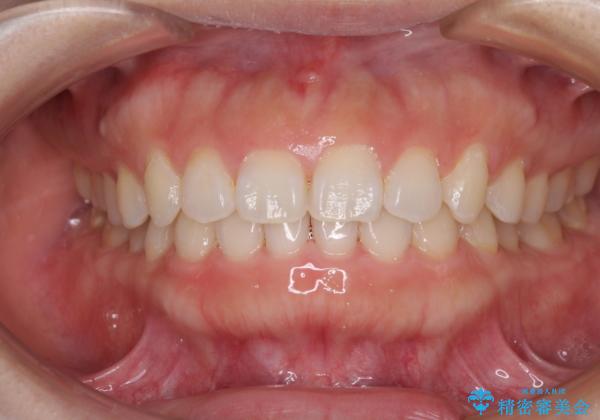

気にしていた口元の印象が改善され、患者様には大変満足していただきました。